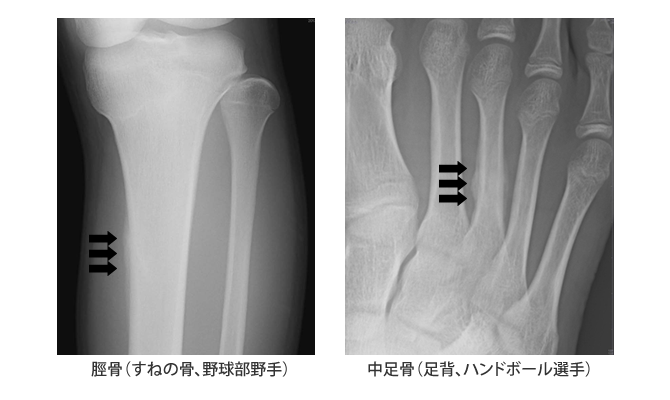

疲労骨折

一方、疲労骨折では長距離走などの慢性的な、小さな外力の繰り返しで骨折してしまう。下記の2症例は、ともに17歳であった(矢印は仮骨形成)